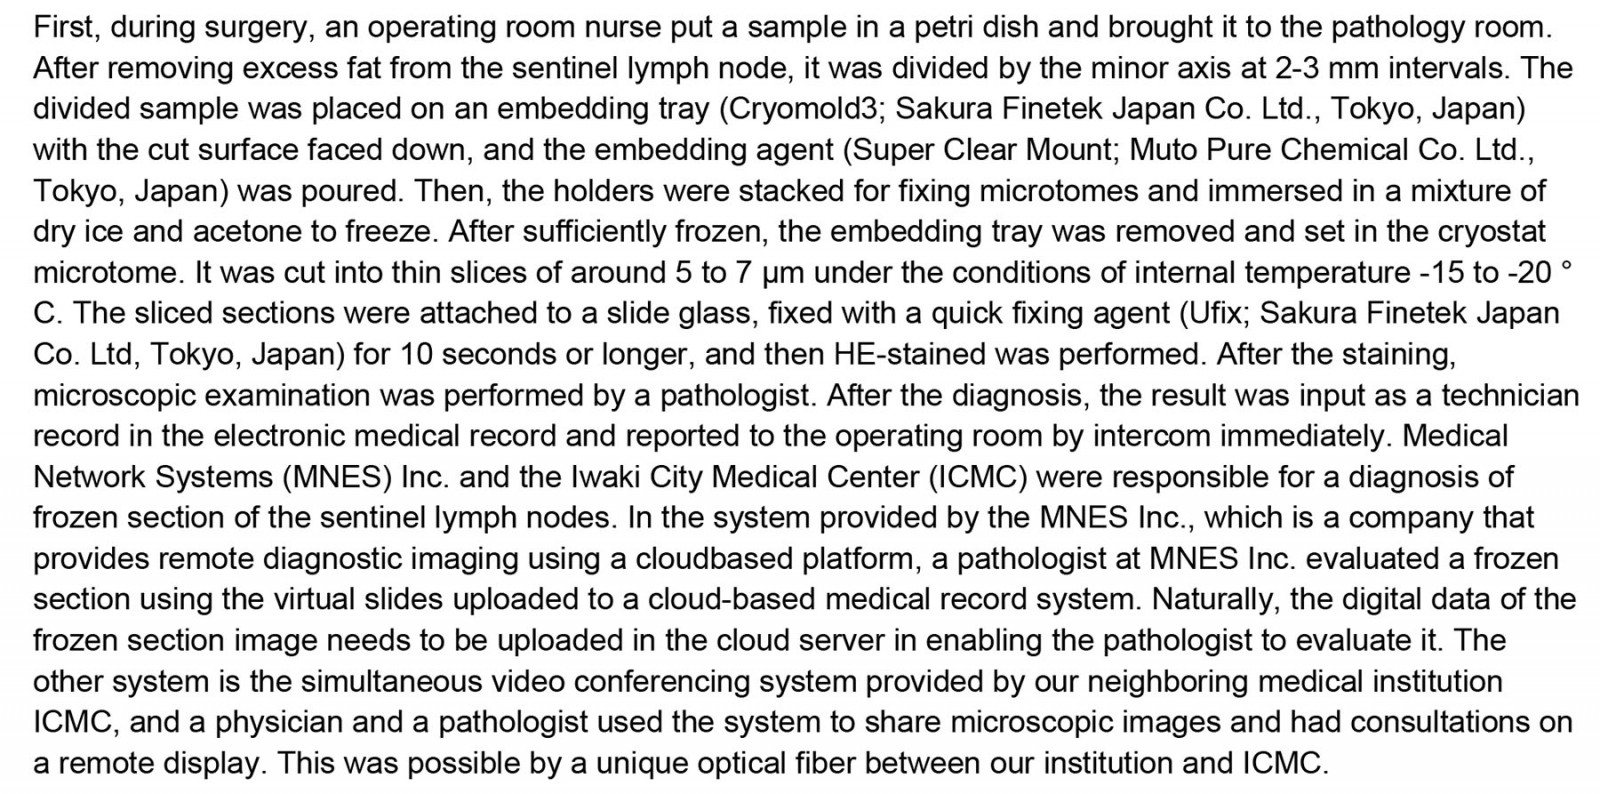

Process of pathological diagnoses, telecommunication technology and related costs

The submitted sentinel lymph nodes, in both systems, were cut at the largest cross-sectional slice for the first few times, and then at a thickness of about 2 mm in the short-axis direction. All preoperative and postoperative diagnoses using paraffin section were made by a pathologist who specializes in breast cancer pathology, visiting Jyoban Hospital once a week. Postoperative diagnoses of sentinel lymph nodes consist of not only inspections of paraffin sections but also of frozen sections made during the surgery.

Telepathology for intraoperative frozen section consultations employed one of two distinct types of telecommunication technology, depending on availability: a cloud-based system (responsibility of Medical Network Systems, MNES) or a simultaneous videoconferencing system (responsibility of Iwaki City Medical Center, ICMC).

For the cloud-based system, we created digital slides for frozen sections of sentinel lymph nodes using the digital scanner Nano Zoomer S210 (Hamamatsu Photonics; https://www.hamamatsu.com/jp/ja/product/life-science-and-medical-systems/digital-slide-scanner/C13239-01.html), which allows a magnification of 80 times at maximum, and uploaded them to the server. This is one of the few systems eligible for reimbursement under the Japanese national health insurance scheme and is considered to enable a comprehensive slide examination of the slides through digital imaging, ensuring a diagnosis that is on par with the traditional pathological diagnosis conducted using a microscope. However, the system may present difficulties in easily focusing on slides with significant thickness.

Pathology diagnoses were made using the viewing software LOOKREC (MNES Inc.; https://mnes-lookrec.com), which allows a magnification set by a digital scanner at maximum.

Eye Vision NEO (ENWA; https://www.enwa.tv/eyevision-neo) was used as the videoconferencing system, cellSens Standard (Olympus; https://www.olympus-lifescience.com/ja/software/cellsens) as microscope image viewing software, and SS-VPN (Shonan Tech, Kanagawa, Japan) as the virtual private network line, specifically prepared for the ICMC and Jyoban Hospital to connect the two hospitals.

The costs of the systems are shown in Table 1. Other details of intraoperative frozen section consultations using telecommunications technology are summarized in Supplementary text 1.

Table 1: Costs of the MNES and ICMS systems

We report the use of two types of telepathology technology with comparable diagnostic accuracy. The cloud system took a longer time than the simultaneous videoconferencing system, and this may be affected by the time it takes to upload the images, and data transfer speeds. The current simultaneous videoconferencing system has the advantage in terms of speed as it is connected by the virtual private network. Further, in this study, the cloud system incurred more initial costs (mostly for the digital scanner) and running costs than the simultaneous videoconferencing system. In this sense, the simultaneous videoconferencing system may have been more advantageous than the cloud system both in terms of time and financial aspects in this small sample study.